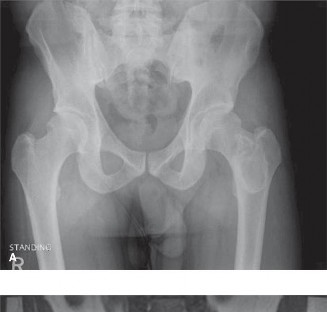

Initial Radiographs (Left Femur):

Anterior-posterior (AP) and lateral views of the left femur were obtained. These revealed a displaced, comminuted, transverse fracture of the mid-diaphyseal femur. Critically, associated with the fracture was a large, expansile, lytic lesion occupying nearly the entire mid-diaphyseal segment. The lesion exhibited the classic "ground-glass" matrix appearance, which is highly characteristic of fibrous dysplasia. Significant cortical thinning and endosteal scalloping were evident along the length of the lesion. There was no overt periosteal reaction indicative of aggressive malignant change, nor was there clear evidence of osteoid or chondroid matrix production within the lesion itself, apart from the ground-glass pattern. Cortical breach was clearly visible at the fracture site. No obvious extraosseous soft tissue mass was identified on plain films.